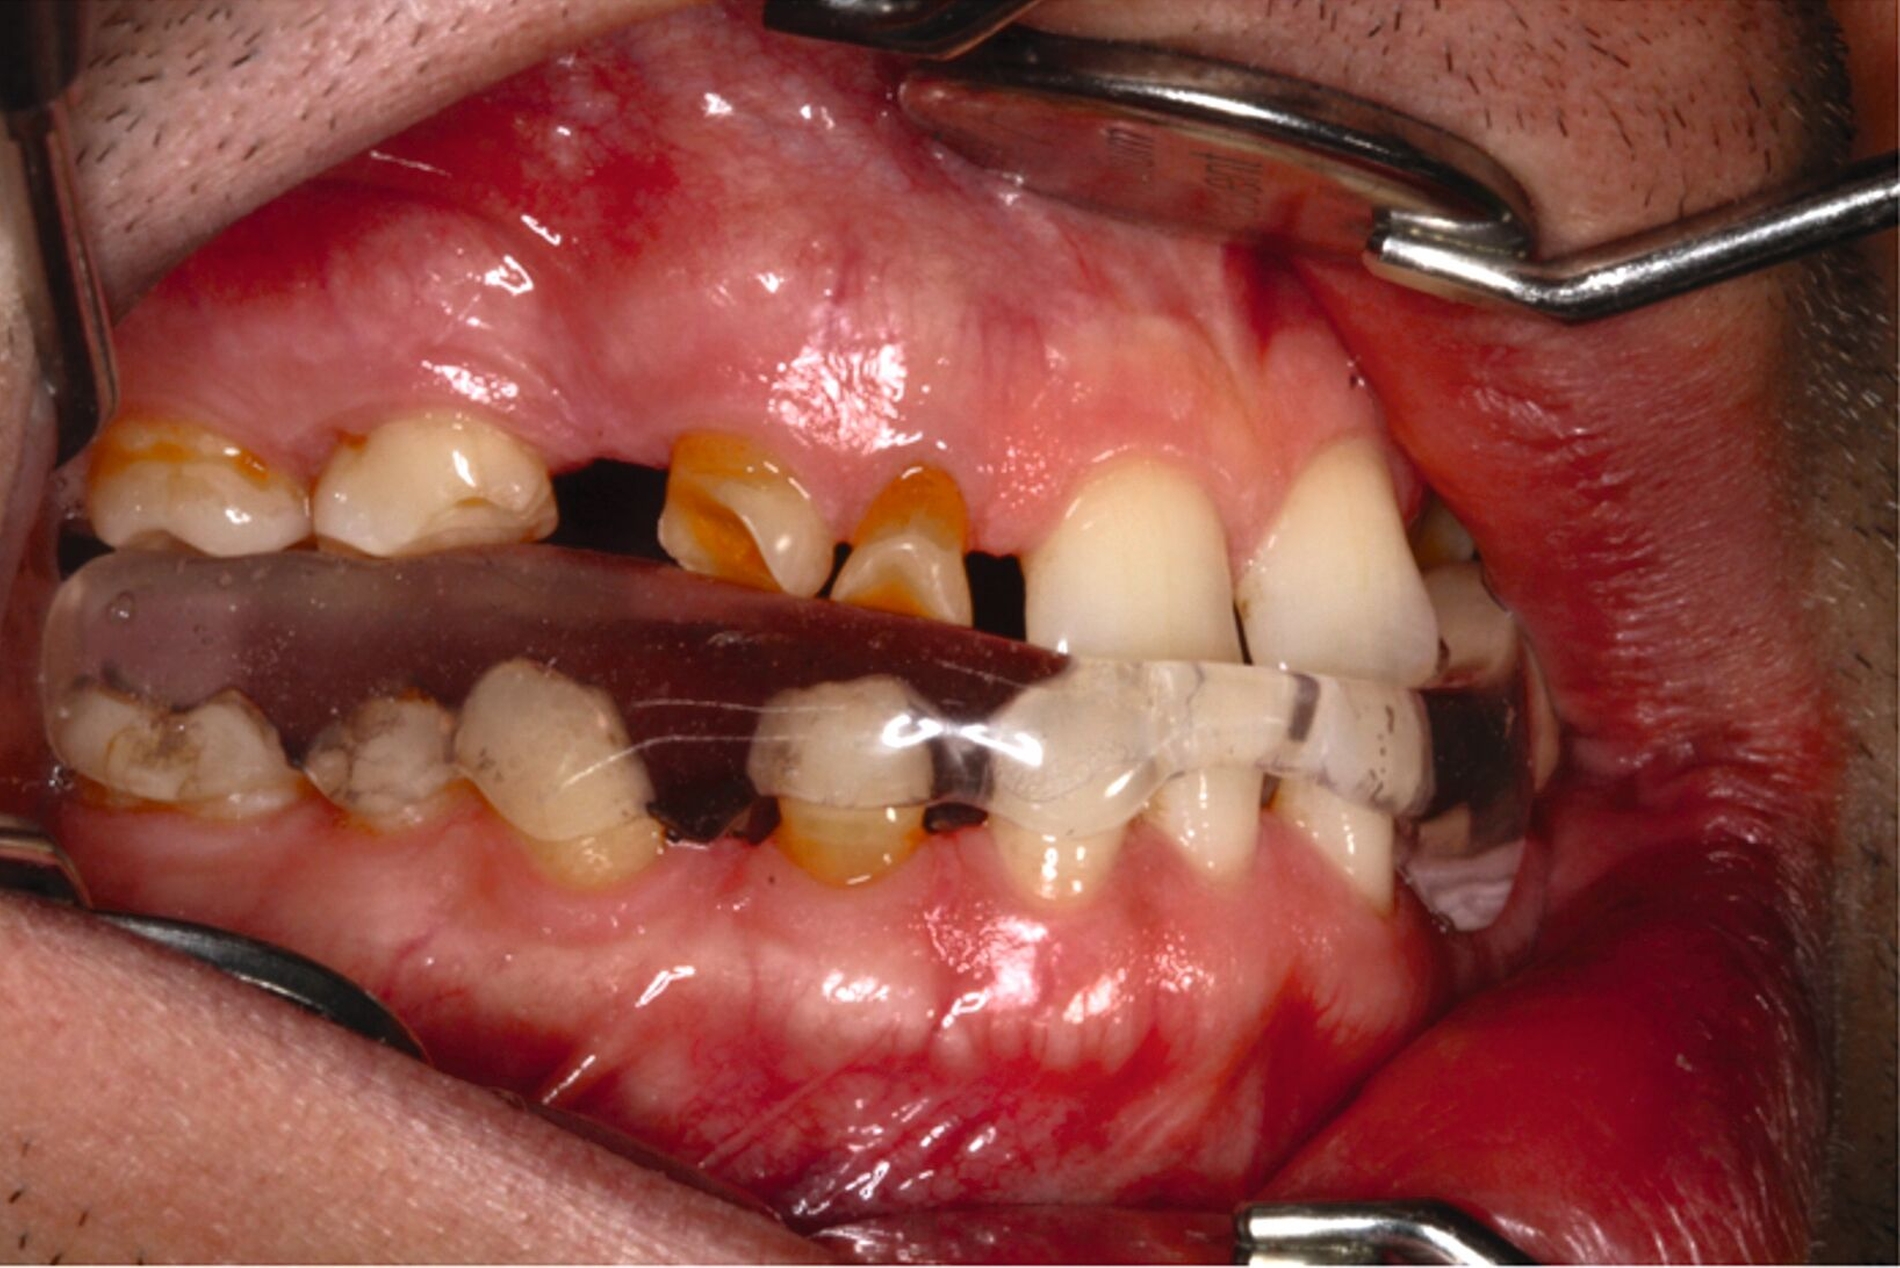

Eine mögliche und indizierte Umstellungsosteotomie wurde vom Patienten abgelehnt. Da seitens des Patienten eine Kopfbissstellung möglich war, wurde eine Bissumstellung und -hebung mit nur noch geringgradigem Vorbiss und anschließender Zahnimplantation in Erwägung gezogen. Begonnen wurde mit einer temporären Schienentherapie zur Neuorientierung der Bisslage (Abbildung 3). Da der Patient die angepasste Bisshebung tolerierte, wurde diese nach Entfernung der persistierenden Milchzähne 55, 53, 52, 62 und 83 temporär mittels einer Valplastprothese (Abbildung 4) als Interimsersatz im Oberkiefer gesichert.